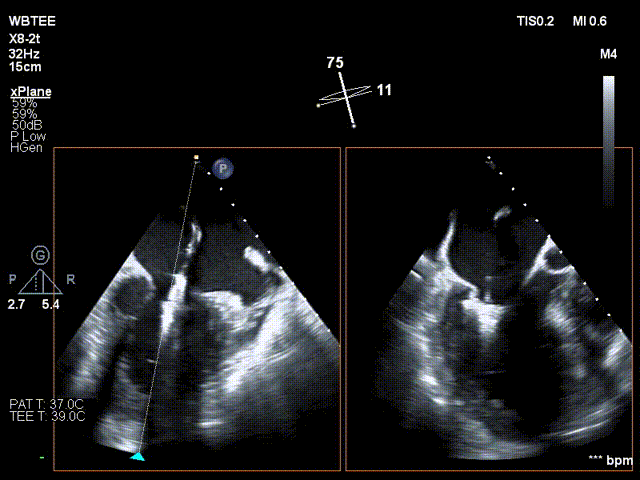

患者全身麻醉消毒铺巾后,建立右侧股静脉入路,在经食道超声指导下精准穿刺房间隔。将可操控导引导管和二尖瓣夹XTR输送系统送入左心房

标准房间隔穿刺

XTR进入左心房

置入SGC系统

调整二尖瓣夹轨迹和方向,使其轨迹垂直于二尖瓣环平面且指向心尖,定位于二尖瓣2区且6-12点钟方位

XTR弹道轨迹测试

XTR定位12-6点